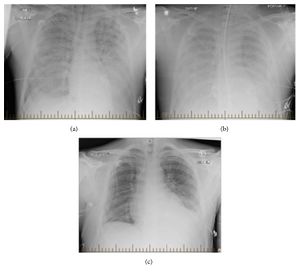

Progression of hantavirus pulmonary syndrome | |